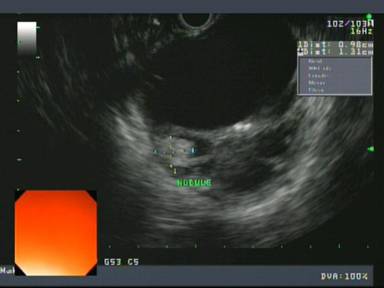

A fifty-two-year-old male presented with a 2-year history of epigastric abdominal pain radiating to his back with associated nausea and varying lengths of time. He had presented with similar symptoms to the emergency room one month prior, had abdominal imaging showing a lobulated cystic lesion in the tail of the pancreas, and was asked to follow up with his gastroenterologist. His past medical history was significant for alcohol and intravenous drug abuse, chronic pancreatitis, hepatitis C, uncontrolled diabetes, family history of pancreatic neoplasm, and personal history of MCN of the pancreas twelve years prior status post distal pancreatectomy and splenectomy. He has been seen in and out of the hospital for pancreatitis likely secondary to alcohol use and possibly triglycerides due to uncontrolled diabetes. On physical exam his vital signs were normal and he had epigastric tenderness. His amylase and lipase at the time of evaluation were normal. Contrast-enhanced computed tomography (CT) scan of abdomen/pelvis showed a lobulated cystic lesion in the distal pancreatic body measuring 4.5x6.5x5.8 cm (Figure 1). Endoscopic ultrasound (EUS) with fine-needle aspiration (FNA) showed a 7.5x5.1 cm septated cyst in the body of the pancreas with irregular walls and mural nodules shown within the cyst (Figure 2). Of note, there were at least 2 mural nodules within the cyst on EUS with the largest measuring 13x9.8 mm. Cyst fluid analysis showed an amylase level of 331 U/L and a CEA of 68.5 ng/mL.

Figure 2. EUS image of a 7.5x5.1 cm septated cyst in the body of the pancreas with irregular walls and a measured 1.31x0.98 cm mural nodule within the cyst. |